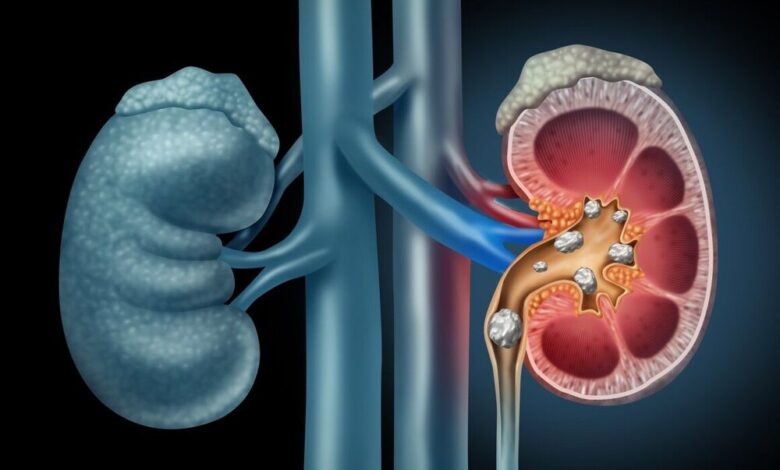

سنگ کلیه یکی از شایع ترین مشکلات در سیستم ادراری است که می تواند باعث درد شدید و عوارض مختلف شود. این سنگها بیشتر به دلیل تجمع مواد معدنی و ترکیبات خاص در کلیه ها است و تحقیقات نشان می دهد که عوامل تغذیه ای نقش مهمی در شکل گیری و پیشگیری از این سنگ ها ایفا می کنند ، بنابراین می توانند به افراد دارای روابط مناسب رژیم غذایی کمک کنند.

مصرف بیش از حد قندهای اضافه شده یکی از عوامل مؤثر در افزایش دفع کلسیم از طریق کلیه ها و در نتیجه تشکیل سنگ ها ادا کردن و این یک کلسیم است و برخلاف قندهای طبیعی در مواد غذایی ، قندهایی که در نوشیدنی های شیرین ، کیک و غذاهای بسته بندی شده پردازش می شوند ، می توانند تعادل مواد معدنی موجود در بدن را مختل کنند و محدود کردن مصرف این نوع غذا گامی مؤثر در کاهش خطر سنگ های کلیه است.

سدیم یکی دیگر از عناصر مهم است که به تنظیم سطح کلسیم در بدن کمک می کند و مصرف بیش از حد سدیم باعث افزایش دفع کلسیم از کلیه ها می شود و خطر رسوب معدنی در دستگاه ادراری را افزایش می دهد و میزان سدیم در رژیم غذایی را به دامنه توصیه شده کاهش می دهد ، علاوه بر مزایای قلبی عروقی ، تأثیر قابل توجهی در کاهش خطر دارد.

پروتئین های حیوانی تأثیر معنی داری بر ترکیب شیمیایی ادرار دارند و مصرف بیش از این پروتئین ها می تواند افزایش یابد. اسیدیته ادرار ، کاهش سطح سیترات و افزایش خطر رسوب ترکیبات کلسیم و ادا کردن تنظیم میزان مصرف پروتئین حیوانی و جایگزینی بخشی از آن با منابع گیاهی یک روش مؤثر برای کاهش خطر سنگ کلیه است.

صالبی خاطرنشان کرد: فیبر رژیم غذایی در دو نوع محلول و نامحلول یافت می شود ، و افزود که فیبر نامحلول موجود در سبوس گندم ، برنج و جو تأثیر قابل توجهی در کاهش سطح کلسیم ادرار دارد و این نوع فیبر با ترکیب کلسیم در دستگاه گوارش ، از جذب بیش از حد کلسیم و کلسیم جلوگیری می کند. علاوه بر این ، افزایش سرعت حرکت مواد در دستگاه گوارش ، فرصت جذب کلسیم را کاهش داده و احتمال تشکیل سنگ کلیه را کاهش می دهد.

الیاف مواد غذایی ، به ویژه فیبر نامحلول در سبوس گندم و برنج ، تأثیر قابل توجهی در کاهش سطح کلسیم ادرار ، کمک به ترکیب با کلسیم در دستگاه گوارش و افزایش دفع مدفوع دارند و علاوه بر این ، فیبر نامحلول باعث حرکت مواد مغذی می شود و خطر کلسیم را کاهش می دهد.